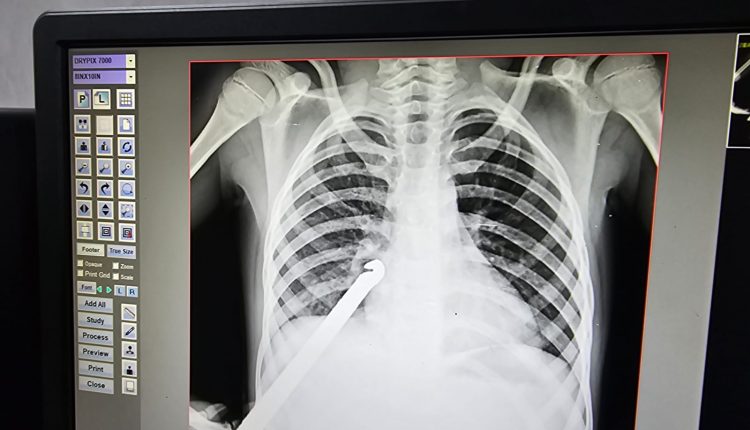

ବରଗଡ଼: ଖେଳୁଥିବା ସମୟରେ ଘଟିଲା ଅଘଟଣ । ନଅ ବର୍ଷର ଶିଶୁ ଦେହରେ ପଶିଗଲା ଲୁହା ଛଡ଼ । ଚିକିତ୍ସା ପାଇଁ ତୁରନ୍ତ ବରଗଡ଼ ମୁଖ୍ୟ ଚିକିତ୍ସାଳୟରେ ଭର୍ତ୍ତି କରିଥିଲେ ପରିବାର ଲୋକେ । କିନ୍ତୁ ସେଠାରେ ଶିଶୁଟିର ଅବସ୍ଥା ଗୁରୁତର ହେବାରୁ ତୁରନ୍ତ ତାଙ୍କୁ ବୁର୍ଲା ବଡ଼ ମେଡ଼ିକାଲକୁ ସ୍ଥାନାନ୍ତରିତ କରାଯାଇଛି ।

ସୂଚନା ଅନୁସାରେ, ଶିଶୁଟି ଭଟଲି ରଥପଡାର ଜୀବନ ପାତିକାର । ଆଜି ସକାଳେ ସାଙ୍ଗ ମାନଙ୍କ ସହ ଖେଳୁଥିବା ସମୟରେ ଅନ୍ୟ ଏକ ନାବାଳକ ସହିତ ତାଙ୍କର ବଚସା ହୋଇଥିଲା । ସାମାନ୍ୟ ବଚସାରେ ଉତ୍ୟକ୍ତ ହୋଇ ଉକ୍ତ ନାବାଳକ ଜଣକ ଘରୁ ଲୁହାରଡ ଆଣି ଜୀବନ ଉପରକୁ ଫୋଫାଡ଼ି ଦେଇଥିଲା  । ଲୁହା ରଡଟି ସିଧା ଜୀବନର ପିଠି ପଟେ ଗଳି ଯାଇ ଅଟକି ରହିଥିଲା । ତୁରନ୍ତ ପରିବାର ଲୋକେ ତାଙ୍କୁ ଡାକ୍ତରଖାନାକୁ ଆଣିଥିଲେ । ଜୀବନର ଅସ୍ତ୍ରୋପଚାର ପରେ ବର୍ତ୍ତମାନ ତାର ଅବସ୍ଥା ସ୍ଥିର ଥିବା ଜଣାପଡିଛି । ସେପଟେ ଖବର ପାଇ ବରଗଡର ସ୍ବେଛାସେବୀ ସଂଗଠନ ସଂକଳ୍ପ ପରିବାର ଭୀମସାରରେ ପହଞ୍ଚି ସମସ୍ତ ଆର୍ଥିକ ସହାୟତା କରିଛନ୍ତି ।